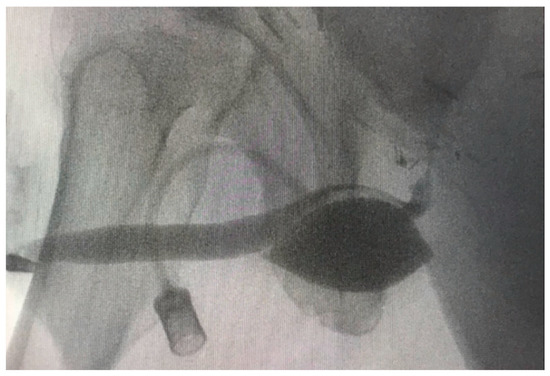

- Delivery of the tip of the tunneller paraurethrally below the hiatus urogenitalis, underneath the membranous urethra. As previously described by Rheder et al. for the fixed male Sling Advance, the entrance of the introducer needle tip into the perineal wound should be in the uppermost corner between the inferior pubic ramus and urethral bulb (Figure 5);